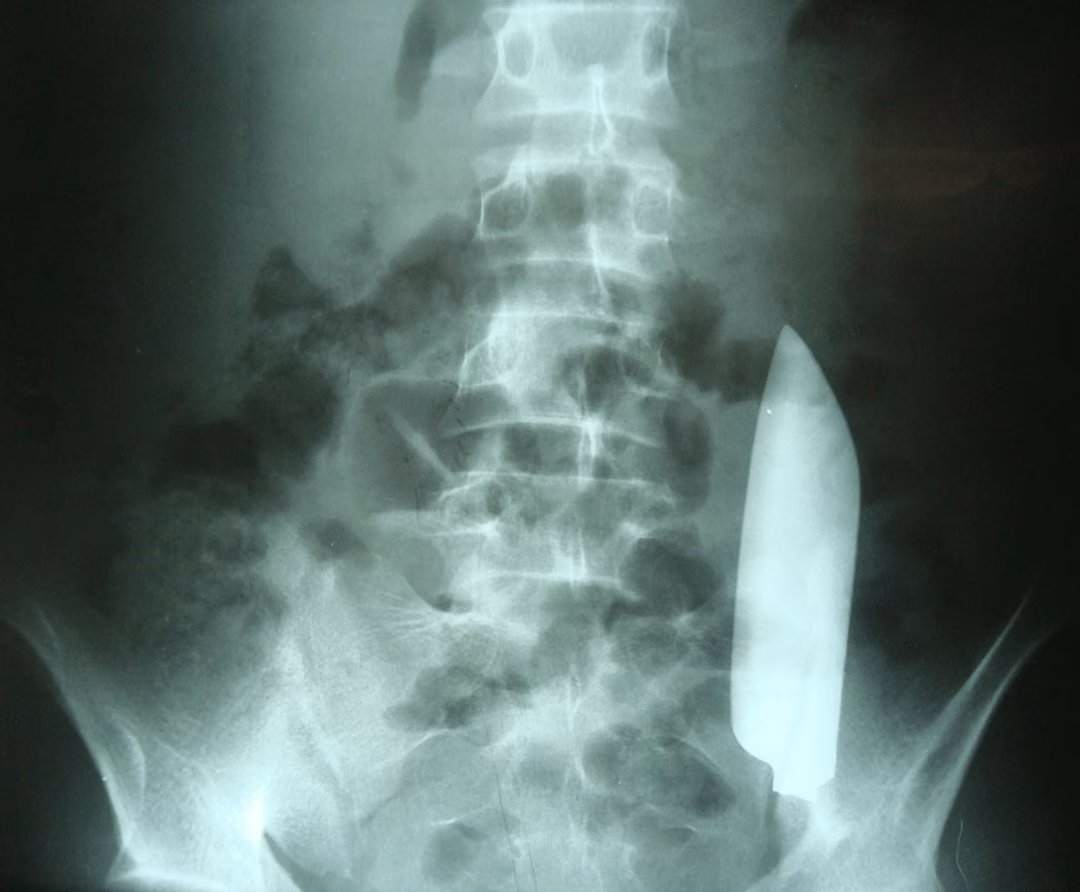

Le jour suivant, les douleurs abdominales s’intensifient et poussent l’homme à se rendre aux urgences. Malgré un examen physique initial peu révélateur, les médecins, par mesure de précaution, prescrivent une radiographie abdominale. Le résultat est stupéfiant : une lame de couteau métallique d’environ 15 cm flotte librement dans l’abdomen du patient, ayant migré du flanc droit vers le flanc gauche.

La radiographie (vue de face) révèle une lame flottant librement dans l’abdomen. © Cureus

Étonnamment, malgré ce déplacement interne, aucun organe vital n’a été gravement atteint. Une petite coupure d’environ un centimètre a toutefois été notée à l’avant du foie. Les médecins estiment qu’elle est due à la blessure initiale et non à la migration de la lame.